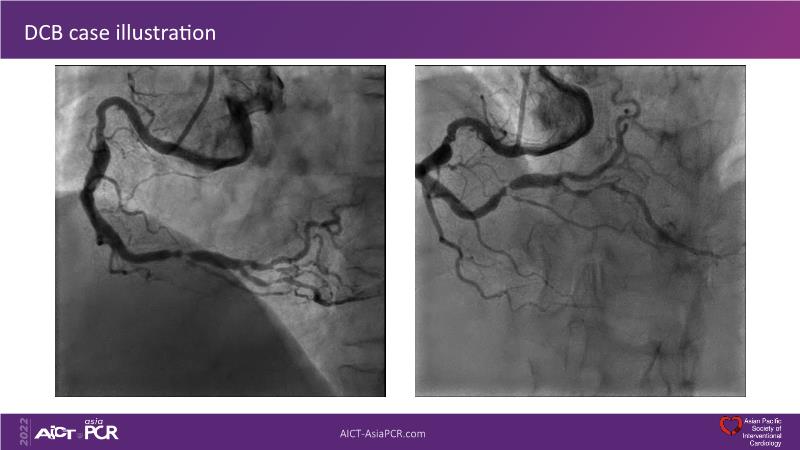

Sirolimus coated balloon: expanding the scope of coronary artery disease treatment

Consult this session to understand the technology and scientific evidence of the novel sirolimus drug-coated balloon, to learn its utility for PCI in a variety of lesion and patient subsets and to understand the evidence and outcomes in real-world patients.

- To learn the utility of the DCB for PCI in a variety of lesion and patient subsets